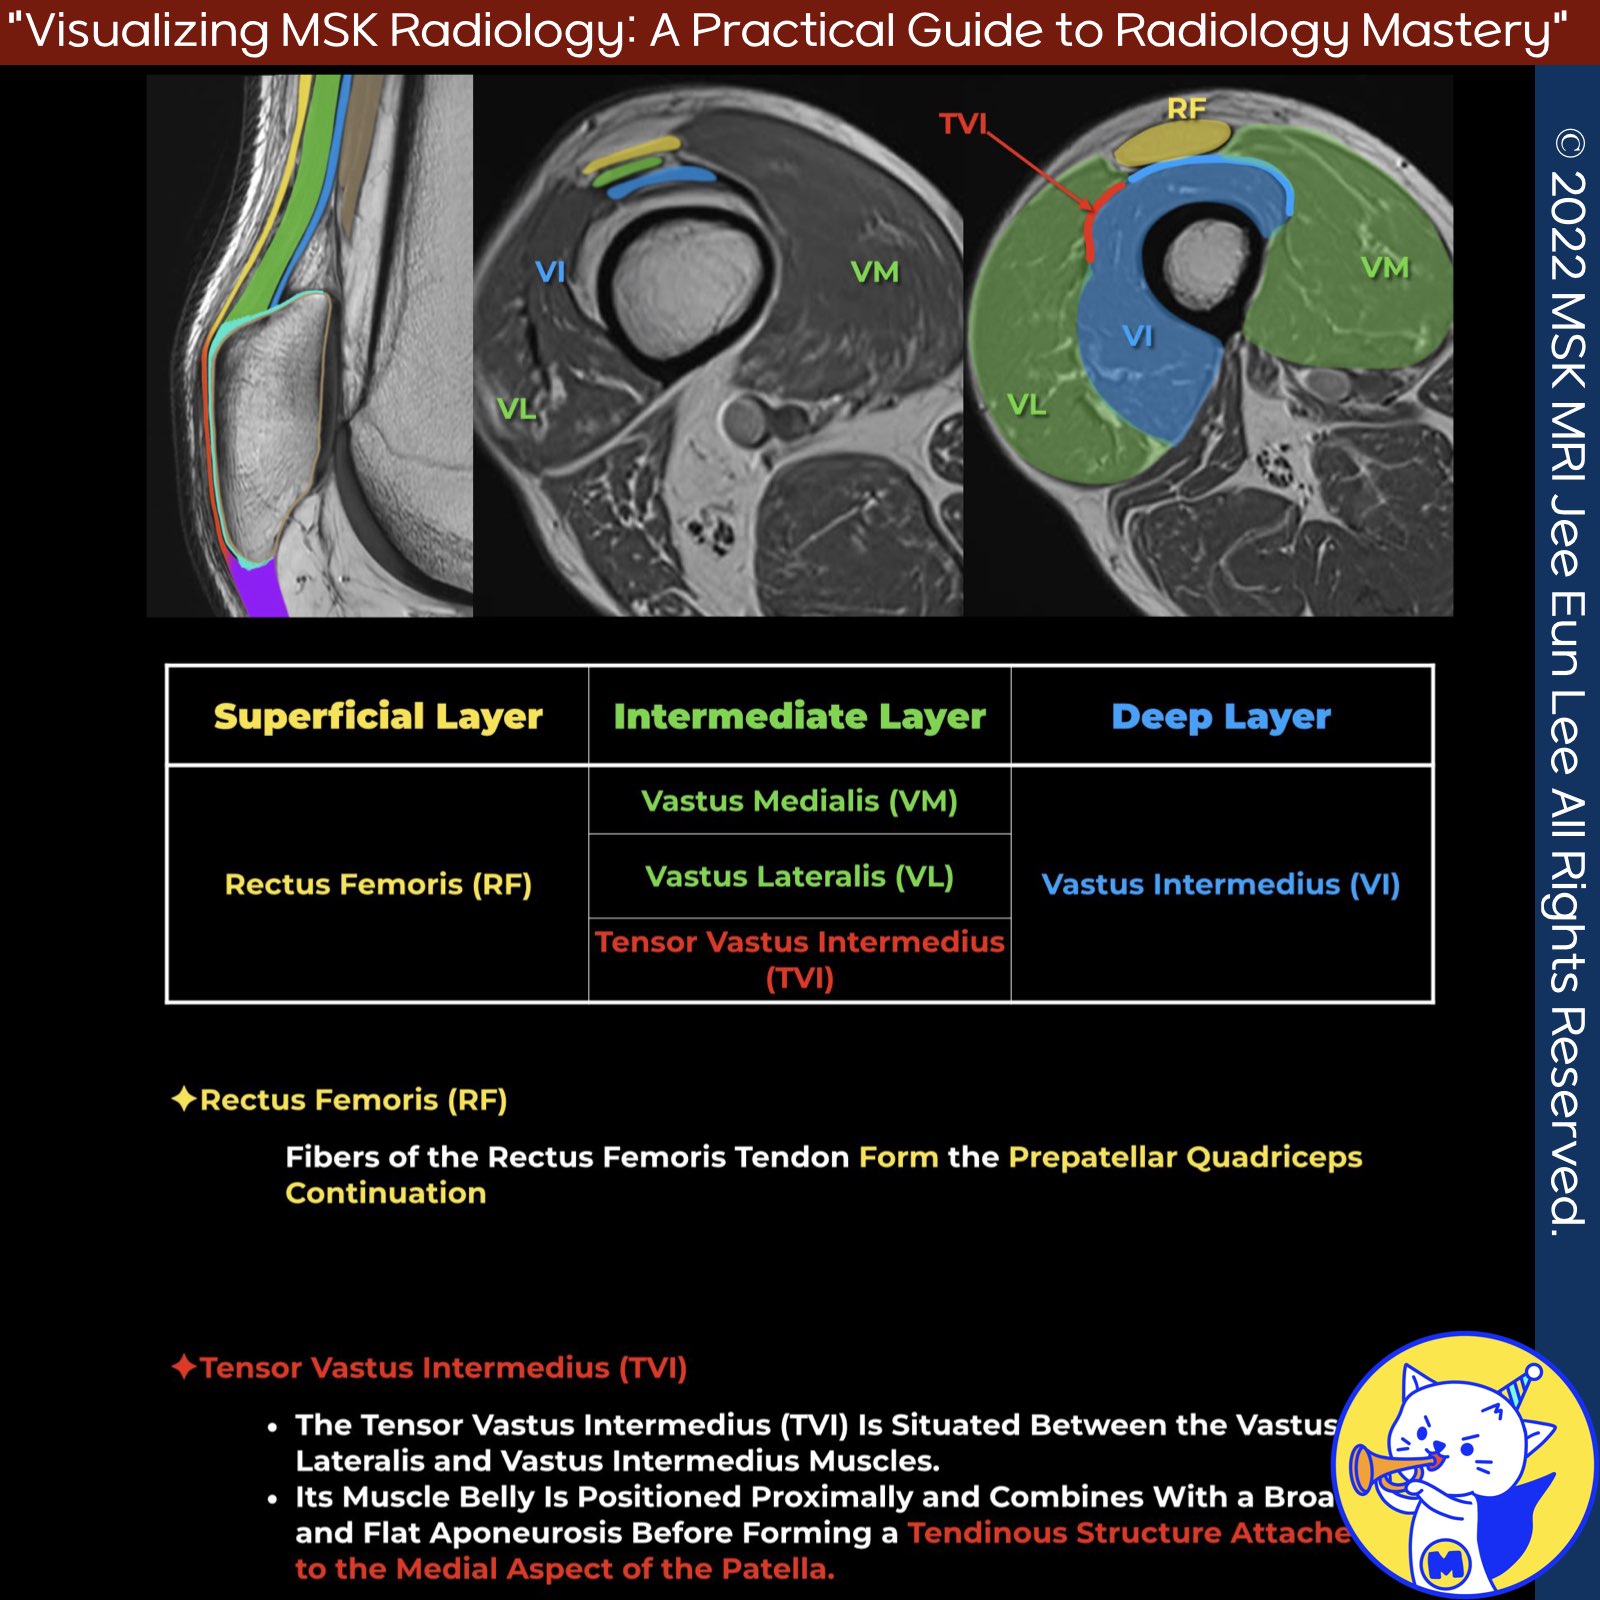

✅ Vastus Muscles and Oblique Fibers:

- The vastus medialis and vastus lateralis muscles have angled fibers called vastus medialis obliquus and vastus lateralis obliquus.

- These fibers attach to the sides of the patella, helping it stay on track during knee movements.

- The medial patellofemoral ligament (MPFL) is a band under the vastus medialis obliquus, stabilizing the patella.

✅ Complex Anatomy of Vastus Medialis:

- The vastus medialis muscle is more complex than it seems.

- It attaches to the patella and quadriceps tendon, and has significant insertions along the aponeurosis of the vastus intermedius muscle.

- This insertion has two parts: a strong front part and a weaker back part.

- Parts of the vastus intermedius muscle also attach to the patella.

- The vastus medialis consists of multiple muscle units at different angles, not just one uniform muscle.

✅ Tensor of Vastus Intermedius (TVI):

- The TVI is situated between the vastus lateralis and vastus intermedius.

- It starts as a muscle and then forms a broad, flat tendon that merges with the quadriceps tendon, attaching to the medial side of the patella.